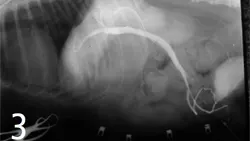

Cystotomy was performed, and mineral composition of these stones was similar to the stones retrieved via the "jiggle technique." Cranial mesenteric arteriography was done to confirm the diagnosis of PSS and to determine whether it was amenable to surgical correction (Figure 2). The portal postcaval shunt was attenuated 75% at the time of surgery, and postattenuation arteriography was performed (Figure 3).

Figure 2. Cranial mesenteric arteriography done during surgery reveals an unusual PSS, presumably following the left gastric vascular flow and entering the caudal vena cava at the level of the caval hiatus. Some intrahepatic arborization is present. This postcystotomy radiograph also confirms that all the bladder stones were removed from the urinary bladder.